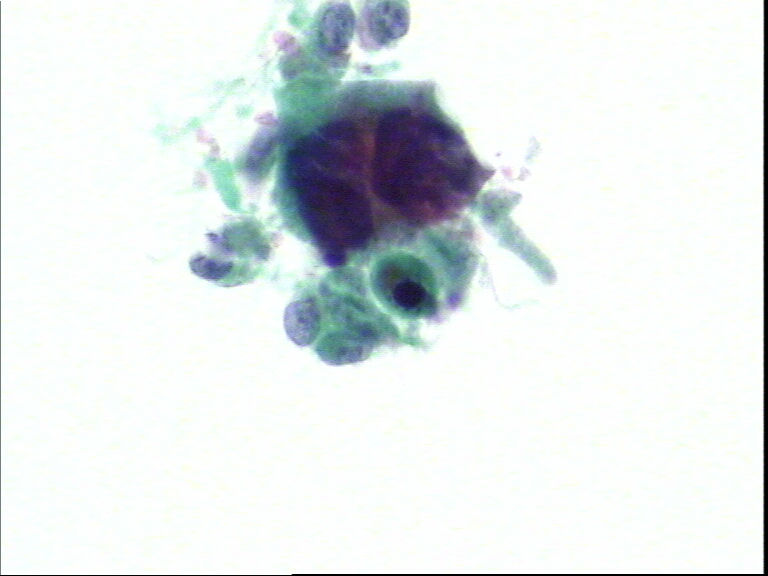

宫颈液基,老年妇女,78岁,临床:宫颈肥大

• 宫颈液基,老年妇女,78岁,临床:宫颈肥大图2

图2

HSIL,建议活检。

HSIL,疑SCC。

HSIL,不除外SCC建议活检。

宫颈高级别上皮内病变,不除外鳞状细胞癌(建议活检)。